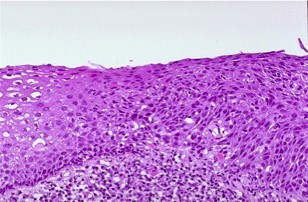

Define Dysplasia, state its main features, results and which tissues are more affected

An abnormal pattern of growth in which some of the cellular and architectural features of malignancy are present (different from metaplasia but occur at the same site, ex. Oesophagus)

What happens in Dysplasia?

Dysplasia is common in:

State the difference between Low Grade and High Grade Dysplasia